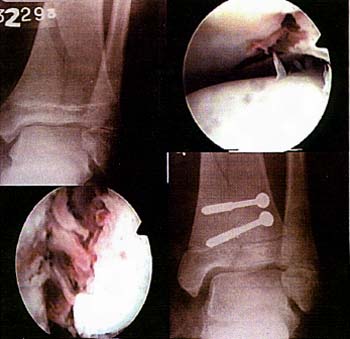

Caso AM sexo femenino - 14 años

Caso HN sexo masculino - 38 años